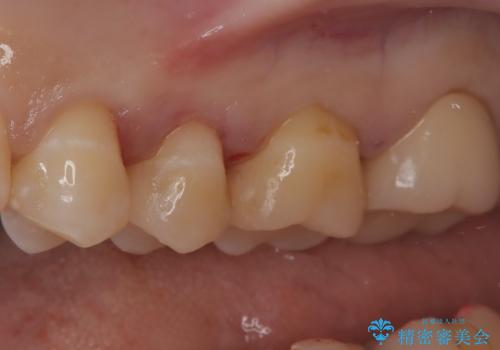

【セラミックインレー】虫歯の治療

- 定期検診にて虫歯を認めたため、セラミックインレーにて治療を行いました。

治療時にはラバーダムを装着しております。